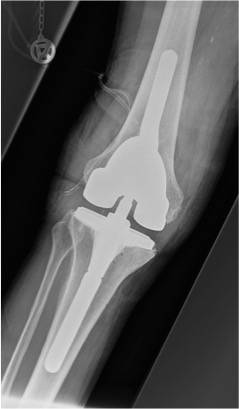

Eine Röntgenaufnahme nach ausgewechselter Knieprothese.